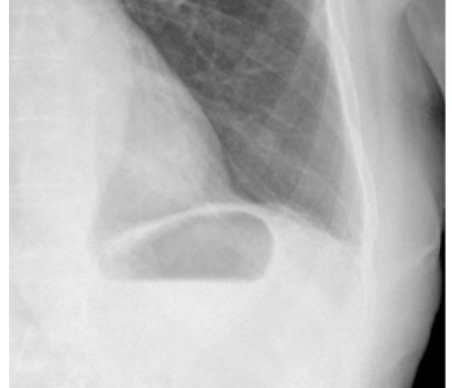

What is this and what type of scan

normal stomach bubble, axr